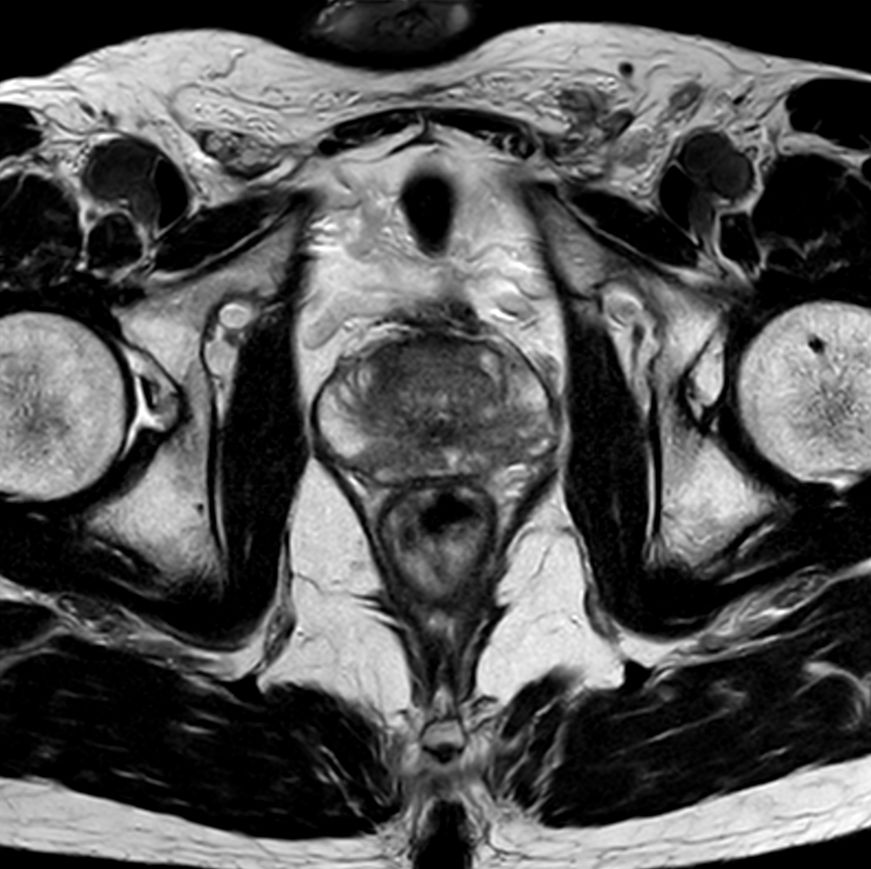

For prostate exams, the MSK M coil can be used in combination with the posterior coil, delivering exceptional quality MR images and high patient satisfaction.

Premium signal-to-noise ratio is achieved via dStream, providing outstanding image resolution.